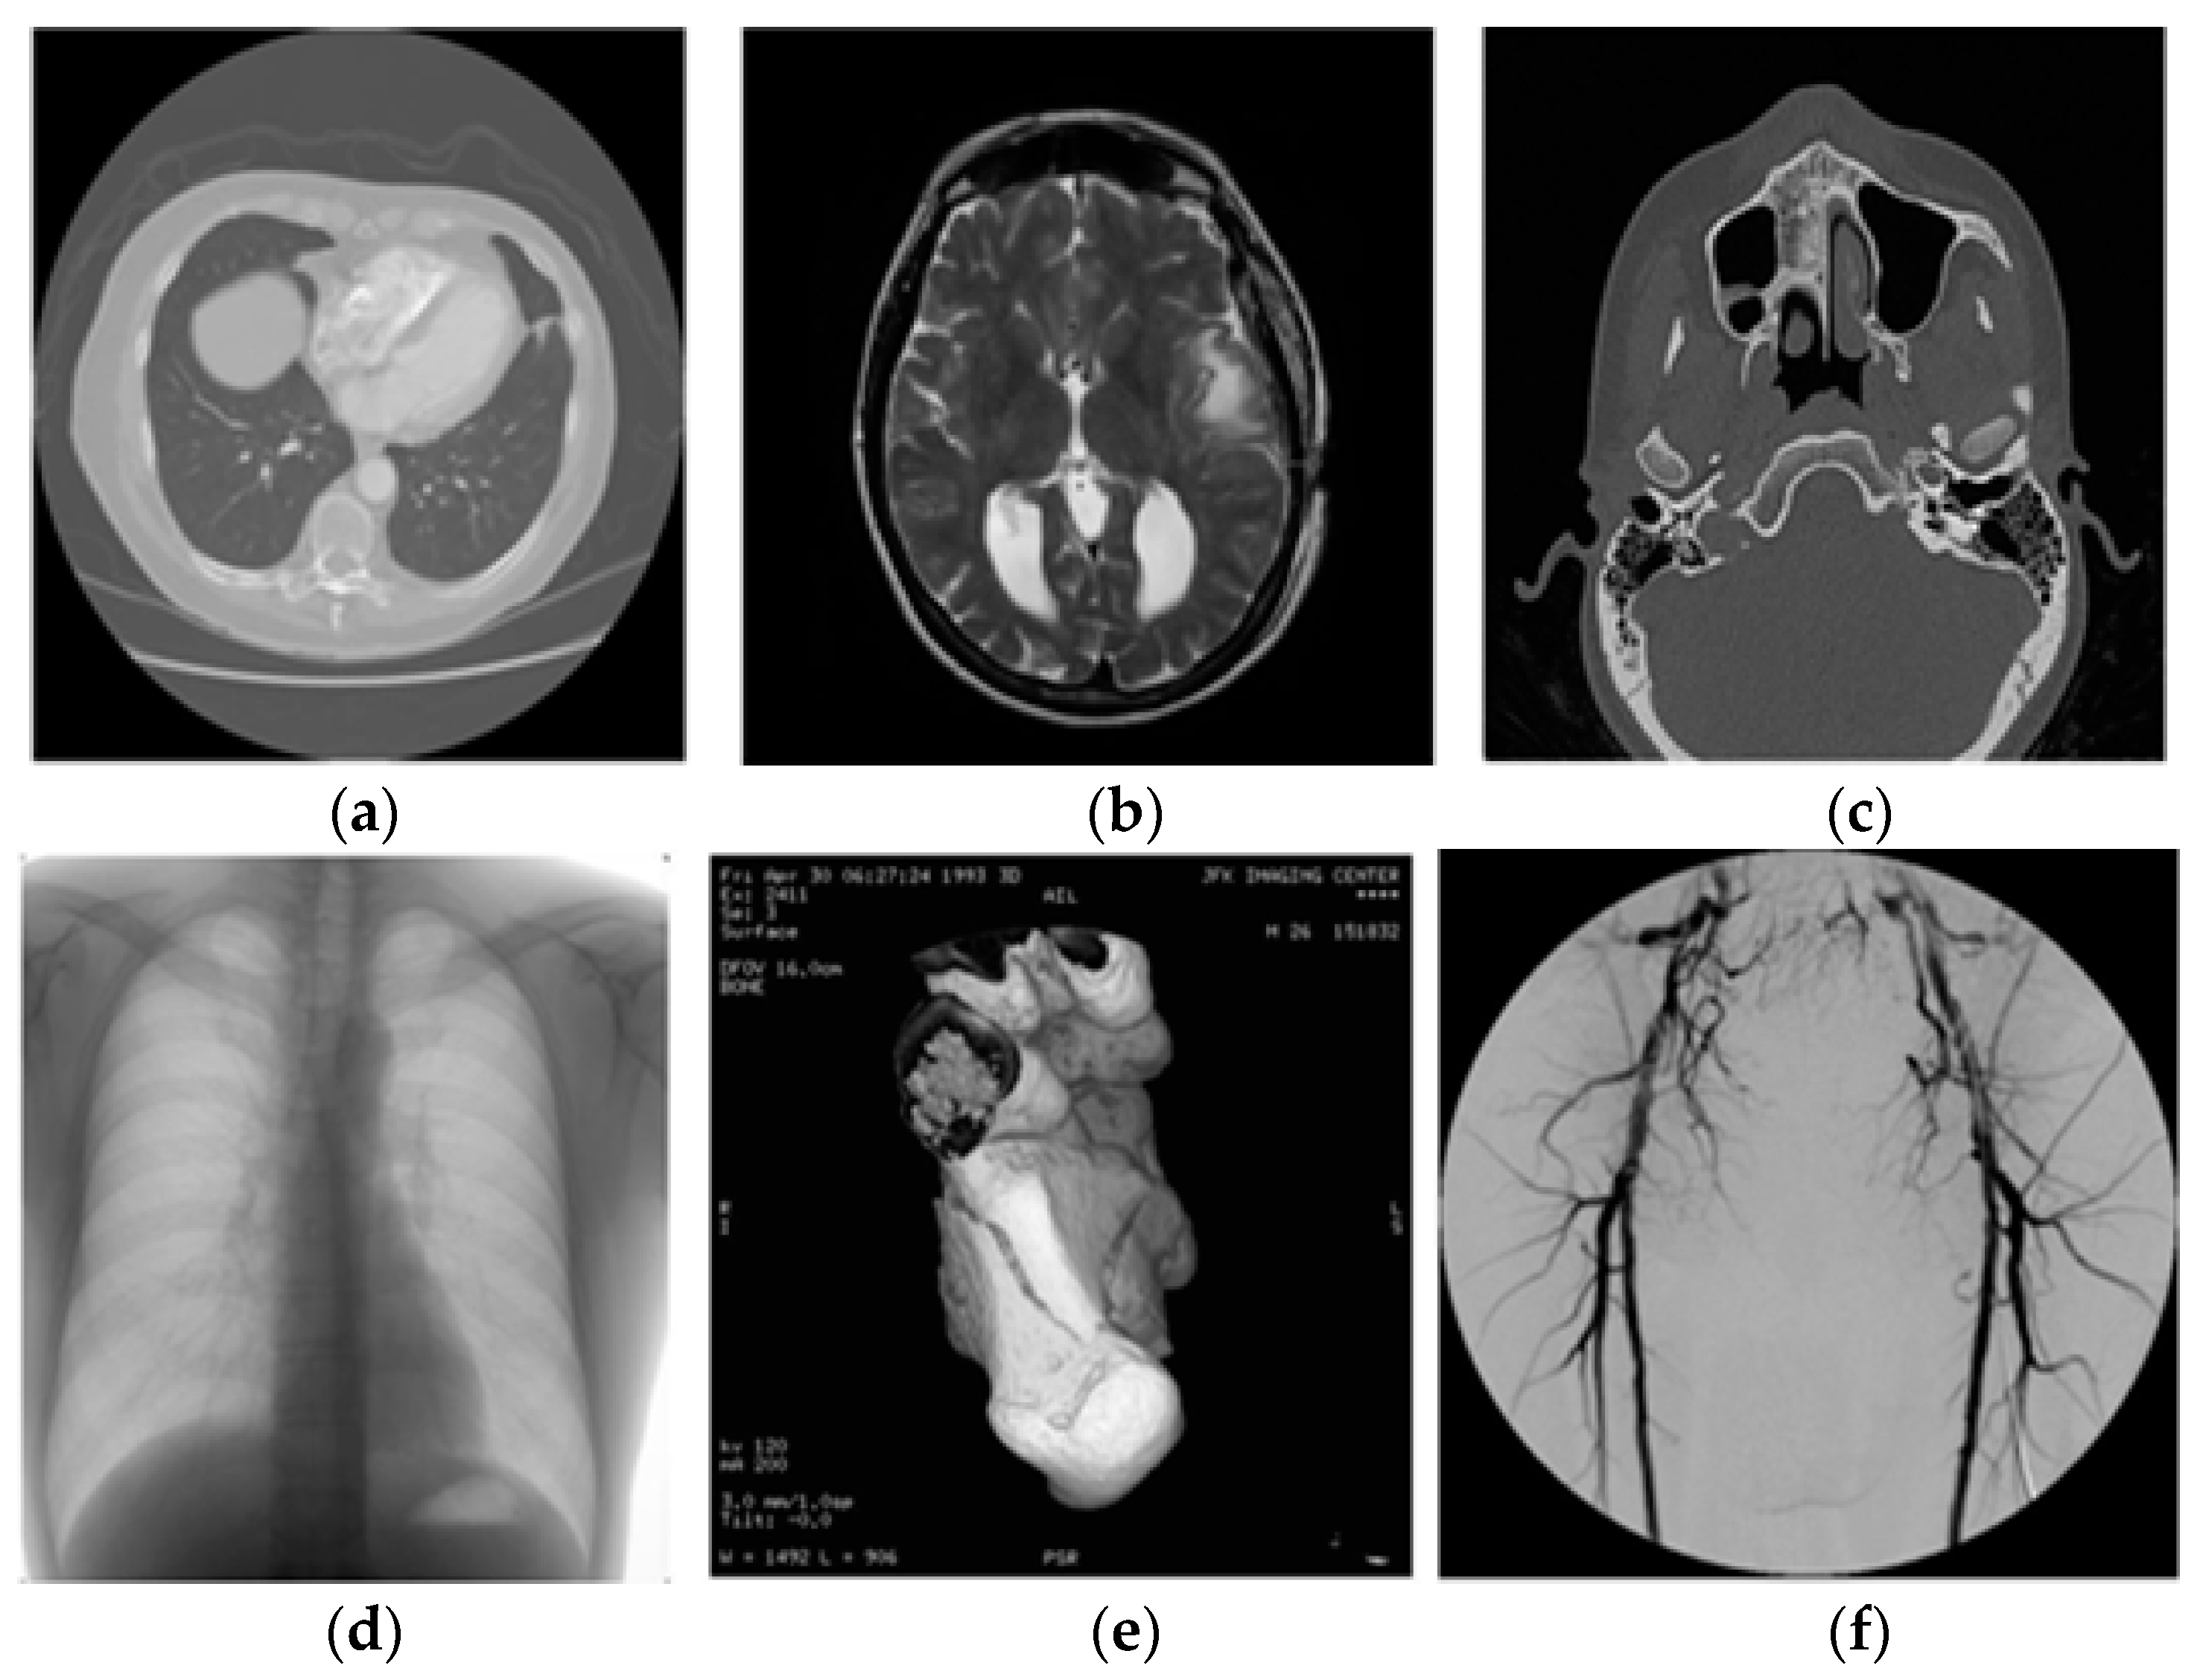

Figure 6 shows the test images. Figure 7 shows the few decomposed images using lifting. Figure 8 and Figure 9 show the watermarked images along with PSNR, MSSIM, and ‘K’ values and also the restored images, respectively. From Figure 8 and Figure 9, it is cleared that the watermark is embedded in the DICOM host image without decreasing the fidelity/quality of the image. Moreover, the image is restored completely by the proposed scheme.

Figure 6. Original host image: (a) Lung, (b) MRI-1, (c) MRI-2, (d) Chest, (e) Ankle, (f) Retina.